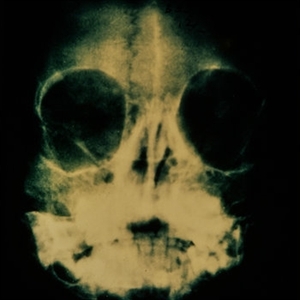

Retinoblastoma

Dec 22 2014 by H. Michael Lambert, MD

Hisopathologic section with rosettes.

Condition/keywords: retinoblastoma